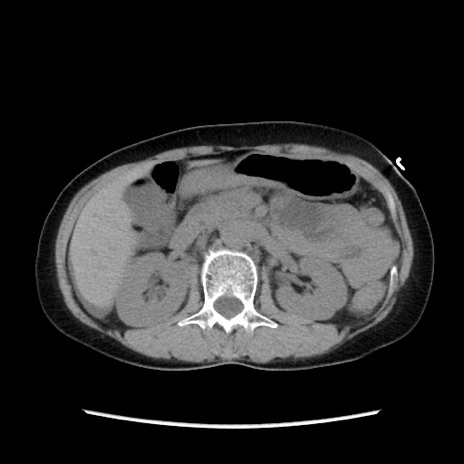

症例32(横断像)

【症例】40歳代 女性

【主訴】上腹部痛、嘔気・嘔吐

【現病歴】約9時間前頃から急に上腹部痛、嘔気、嘔吐が出現。改善しないため救急要請。

【既往歴】子宮頚癌(広汎子宮全摘術、放射線療法)、腸閉塞

【身体所見】腹部:平坦、軟、腸雑音亢進、上腹部を中心に腹部全体に圧痛あり。

【データ】WBC 8400、CRP 0.03